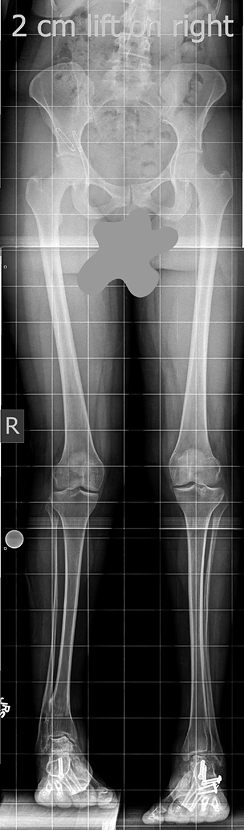

Lisa came to the International Center for Limb Lengthening (ICLL) having already had a dozen surgeries elsewhere to address her bilateral clubfeet. She went to several hospitals looking for help for her painful arthritic ankles and was often given the suggestion of having a total ankle fusion. She shares that she even wondered if she would possibly have to amputate her feet in the future. When Lisa was told it would be helpful to fix her limb length discrepancy before further addressing her feet, she was referred to the ICLL. Dr. Herzenberg recommended that she lengthen her shorter leg with the Precice internal lengthening system.

“Once I knew I could legitimately make myself even, all I could feel was excitement. I would tell anybody looking into this to prepare for a longer recovery than originally planned, especially if you are a woman beyond your twenties.” In addition to keeping expectations for bone healing rates flexible, she suggests patients “over-plan” all the logistics and use high quality supplements to support bone and tissue growth. “Plan for the growth pain and the hard work of physical therapy,” she warns, “but be excited at the prospect of standing even. I was finally even after 20 years of asymmetry.”

Lisa adds, “The entire process has been difficult, probably because I had arthritis in both ankles and they increased significantly in pain post the pin surgery…. Regardless, there has been vast improvement in the way I walk and just the way I stand. It has been an arduous learning process, because all my functioning had to respond to the realignment of my body. But a year and a half after surgery, I have seen the benefits, have come a long ways, and expect to go further.”

“Good has already come of it, because I now have the AFO [Ankle Foot Orthotics], Fabtech Braces, which protect my arthritic ankles, but assist me to be more athletic. These orthotics are likely better because my legs are even…. In the long run, the limb lengthening accomplished what it was supposed to, and I am very glad I did it, and I know my hips are already thanking me. Someday as I decide what to do with my feet, I think it will be more successful because my legs are now even.”